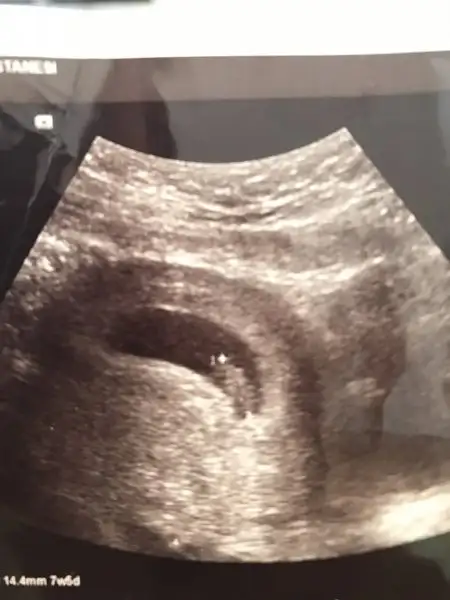

Yapıyor canım özeldede çok pahalı bişey değil 2li test 100 lira falandı ben silivride oturuyorum bizim özel hastaneler çok kötü doktorlar falan çorluya özel muaynaneye gidiyorum oyüzden devlet hastanesinde yaptırdımDevlet hastanesi 2li test yapıyo mu?? Ben yapmadığını okumuştum internette şaşırdım sevindim, özellerde pahalı mı bu test acaba sormak aklıma gelmedi gittiğimde![]()